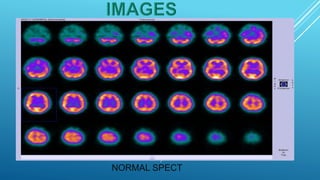

This document provides information about brain perfusion SPECT imaging, including: - It uses radiopharmaceuticals like Tc-99m HMPAO and Tc-99m ECD that cross the blood-brain barrier and distribution corresponds to regional cerebral blood flow. - It is used to evaluate conditions like dementia, head injuries, cerebrovascular disease, and inflammation. - Contraindications include pregnancy and non-cooperative patients. - Patient preparation involves a quiet environment during radiotracer injection and uptake.